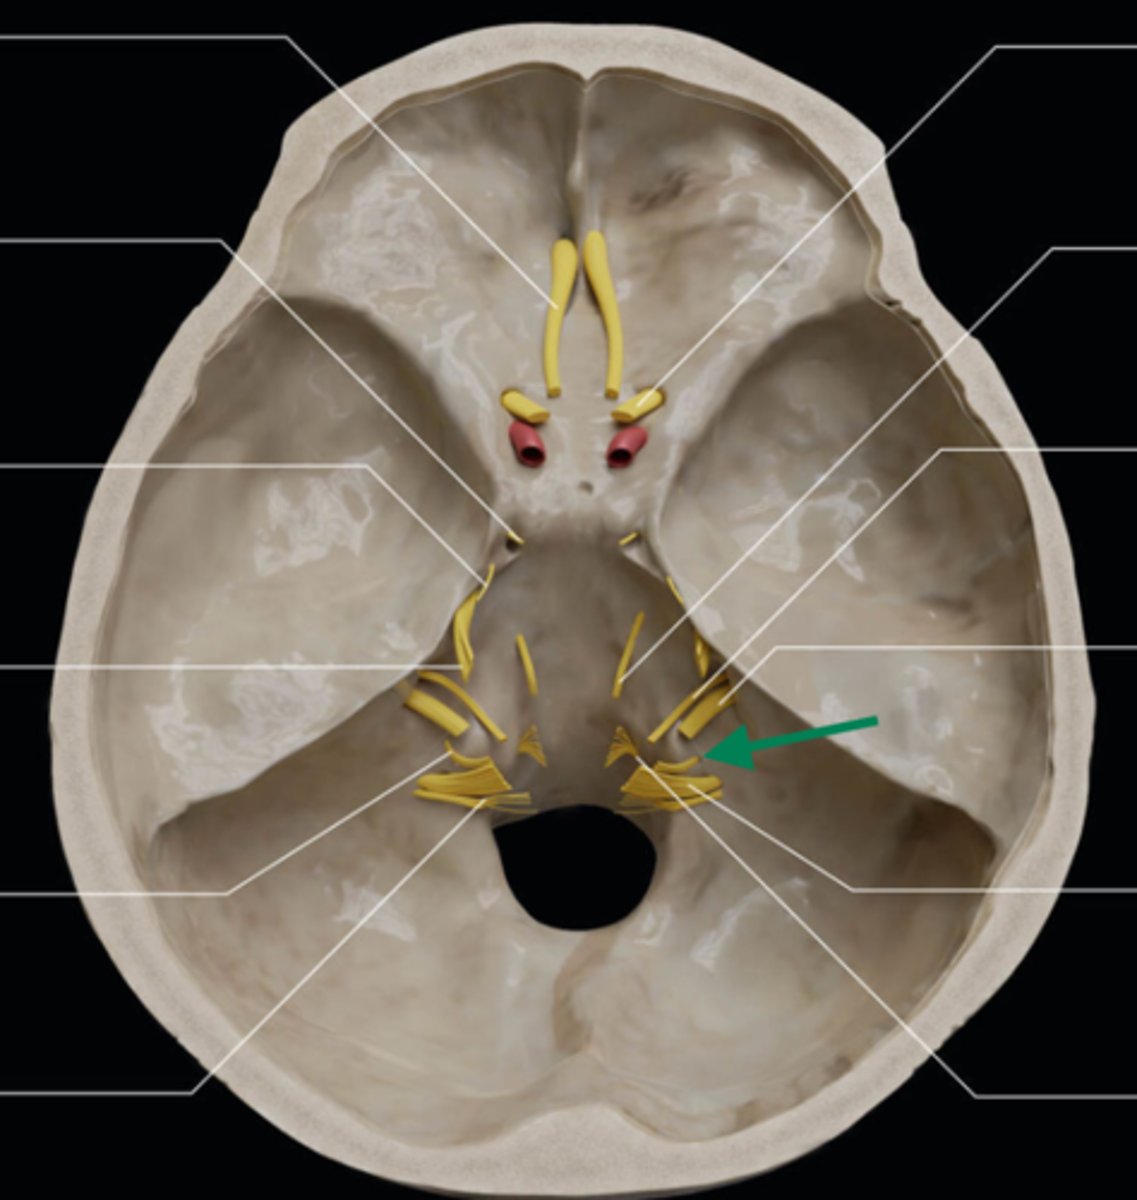

olfactory bulb

olfactory tract

optic nerve (CN II)

internal carotid artery

oculomotor nerve (CN III)

trochlear nerve (CN IV)

abducent nerve (CN VI)

trigeminal nerve (CN V)

facial nerve (CN VII)

vestibulocochlear nerve (CN VIII)

glossopharyngeal nerve (CN IX)

vagus nerve (CN X)

accessory nerve (CN XI)

hypoglossal nerve (CN XII)